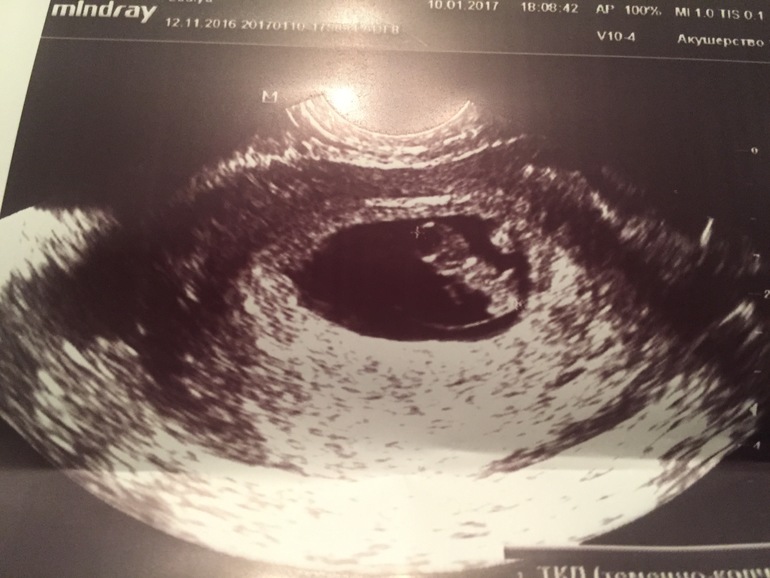

Решила наконец то на узи сходить, на первое свидание с моей бусинкой, заодно и узнать всё ли хорошо, есть ли сердцебиение. Кстати в этот день выделения несколько раз повторились(

На следующий день, 10 января я отправилась в ближайший медицинский центр! Как же мне было страшно на него идти, вы даже себе не представляете...после последней замершей беременности ровно 2 года назад на этом сроке...

Я замерла, врач начала Узи....Включила звук и я услышала, то что я хотела услышать)

Сердечко бьётся 175 ударов в минуту) Срок по месячным и по узи совпал, с моими расчётами тоже, разница буквально в пару дней.

Прикрепился мой эмбриончик по передней стенке.

Единственное, причина тянующей поясницы и выделений это гипертонус(